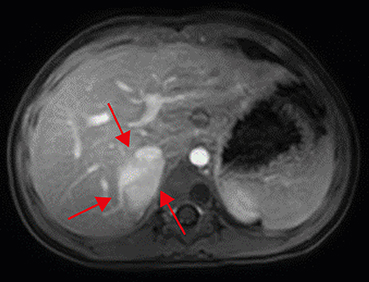

For more detailed examination, magnetic resonance imaging (MRI) was taken. An arterial T1-weighted MRI showed a lobulated mass measuring 3.6×3.8 cm, with high signal intensity, in the right suprarenal area (Fig. 2). Positron emission tomography (PET)-computed tomography (CT) showed hypermetabolism in the right adrenal gland and suggested the need to clarify whether this is a metastatic lesion at the anterior aspect of right psoas muscle (Fig. 3).

Fig. 2

Abdominal magnetic resonance imaging. An arterial-phase imaging shows enhancing lobulated mass (multiple red arrows) in the right suprarenal area, displacing intrahepatic inferior vena cava anteriorly and suspicious of the invasion of right hepatic lobe.